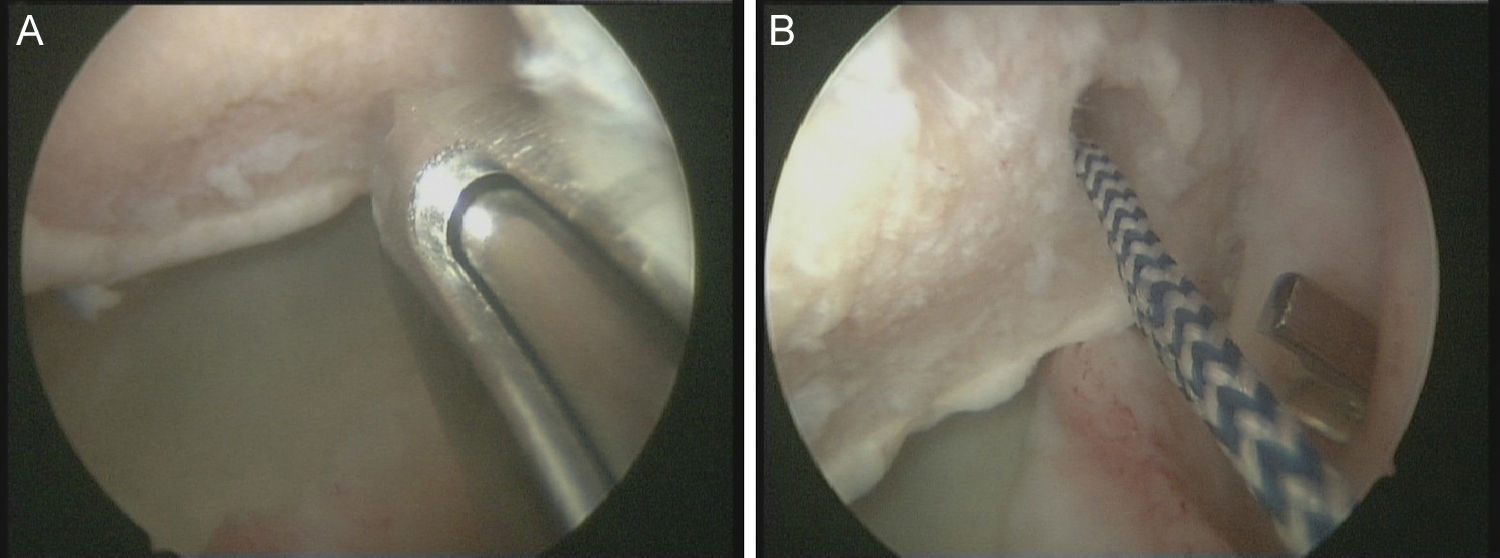

Técnica quirúrgicaBajo anestesia general y locorregional (bloqueo interescalénico), se intenta reducir el hombro de forma cerrada. En caso de no conseguirlo se coloca al paciente en decúbito lateral con tracción de unos 5kg y, siguiendo la técnica descrita por Verma5, se introduce un «Wissinger» por el portal posterior estándar, el que empleamos para la artroscopia de hombro. Con el «Wissinger» a través del portal realizamos tracción de la cabeza humeral hacia lateral, apoyándonos en la cápsula y en la parte posterior del manguito, no en el hueso. Habitualmente con esta maniobra conseguimos introducir la cabeza humeral en la glenoides y podemos pasar a realizar la artroscopia de hombro. En caso de no conseguir una reducción, pasaríamos a realizar una reducción abierta con el paciente en posición de silla de playa y con una vía de abordaje anterior al hombro. Con el hombro reducido se realiza la artroscopia de hombro. Se emplean los portales posterior, anterosuperolateral, anterior, portal de Wilmington y portal posteroinferior. Se estudia la lesión de Hill-Sachs inverso, la relación con el tendón del subescapular y la lesión del labrum posterior (fig. 2, figs. 3 y 4), el resto del labrum y el manguito de los rotadores. Hay que limpiar bien la articulación, extirpar todo el tejido fibroso, liberar el labrum posterior de las adherencias a la glena, preparar el lecho óseo de la glena antes de colocar los implantes (en el caso 1 se emplearon 2 implantes Lupine BR [DePuy Mitek, Raynham, MA], y el caso 2 con un Gryphon BR [DePuy Mitek, Raynham, MA] cargado con doble sutura), realizar la reconstrucción capsulolabral con un pasador directo o indirecto, anudar y cortar las suturas. Una vez reparadas las lesiones soltamos el brazo del sistema de tracción y comprobamos la relación de la cabeza humeral, del defecto óseo anterior con la glenoides, al hacer rotaciones del hombro (sobre todo si hay riesgo de «enganche» con la rotación interna), y decidimos si fijamos el tendón del subescapular en el defecto óseo humeral anterior, tal y como describió Krackhardt6.

No es estrictamente necesario que reproduzcamos un enganche de la lesión de Hill-Sachs inversa para decidir realizar el remplissage inverso. Con la óptica en el portal anterosuperolateral liberamos el tendón del subescapular, su cara anterior y posterior. Preparamos el lecho óseo de la cabeza humeral, extirpando todo el tejido fibroso de la lesión de Hill-Sachs inversa, con el sinoviotomo, la fresa de hueso o periostotomos, hasta obtener hueso sangrante. Entonces desde el portal anterior, insertamos los implante en el defecto óseo (en el caso 1 un 5,5 Healix BR [DePuy Mitek, Raynham, MA] con 2 suturas UHMWPE [Orthocord; DePuy Mitek]) en el tercio superior y en la zona más medial del defecto (fig. 5), y en el caso 2 insertamos 2 Gryphon BR Healix BR (DePuy Mitek, Raynham, MA) con 2 suturas UHMWPE (Orthocord; DePuy Mitek), uno inferior y otro superior en la zona más medial del defecto óseo. Recuperaremos las suturas desde un portal anterosuperior accesorio y con una pinza para atravesar el tendón (Penetratror DePuy Mitek, Raynham, MA) a través del portal anterior, atravesamos el tendón del subescapular y recuperamos las suturas. Daremos puntos colchoneros, uno inferior y otro superior, para conseguir un buen contacto del tendón con el hueso, separando los puntos entre 1 y 2cm (fig. 6). Podemos ayudarnos con un empujanudos a través del portal anterosuperior accesorio para el manejo y recuperación de las suturas, acercándolas a la boca de la pinza penetrator, tratando de no mover en exceso la pinza una vez atravesado el tendón, para evitar lesionar el tendón y el cartílago. Manteniendo el brazo en 35-40° de rotación interna anudamos primero el punto inferior y luego el superior (figs. 7 y 8).